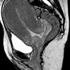

porod, snemanje, magnetna resonanca Sprednji pogled glave otroka v medeničnem vratu. Žurnal24 porod, snemanje, magnetna resonanca